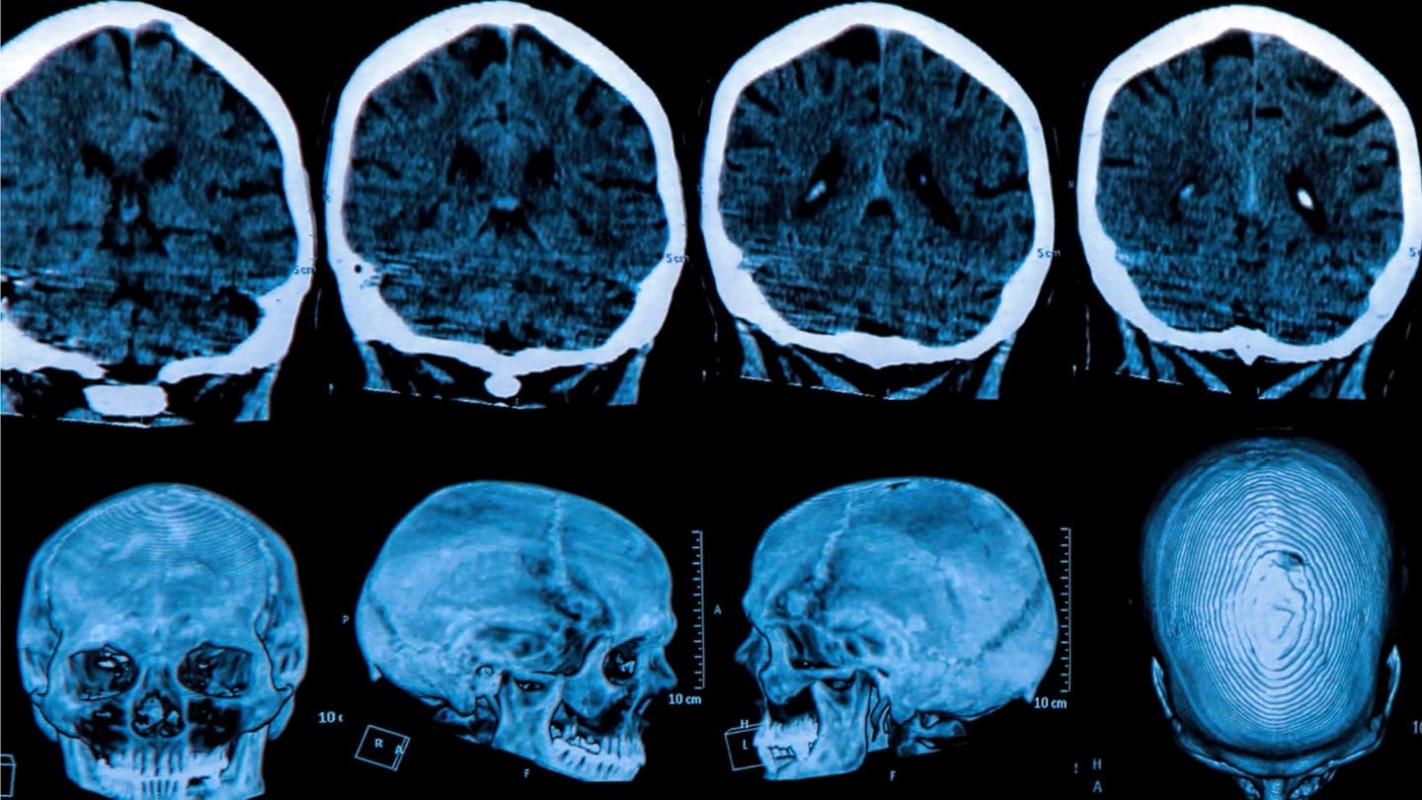

Quienes la padecen describen a la enfermedad neurodegenerativa de Huntington como tener Parkinson, Alzheimer y una afección neuronal al mismo tiempo.

Los investigadores inyectaron un innovador medicamento en el fluido espinal de 46 pacientes y consiguieron reducir los niveles de proteínas tóxicas en el cerebro y, por lo tanto, avanzar en un posible tratamiento.

La enfermedad de Huntington es causada por un error en un pequeño tramo del ADN llamado gen de la huntingtina.

Generalmente, este contiene las instrucciones para crear la proteína huntingtina, que es vital para el desarrollo del cerebro.

Pero un error genético corrompe la proteína y la convierte en un asesino de las células cerebrales.